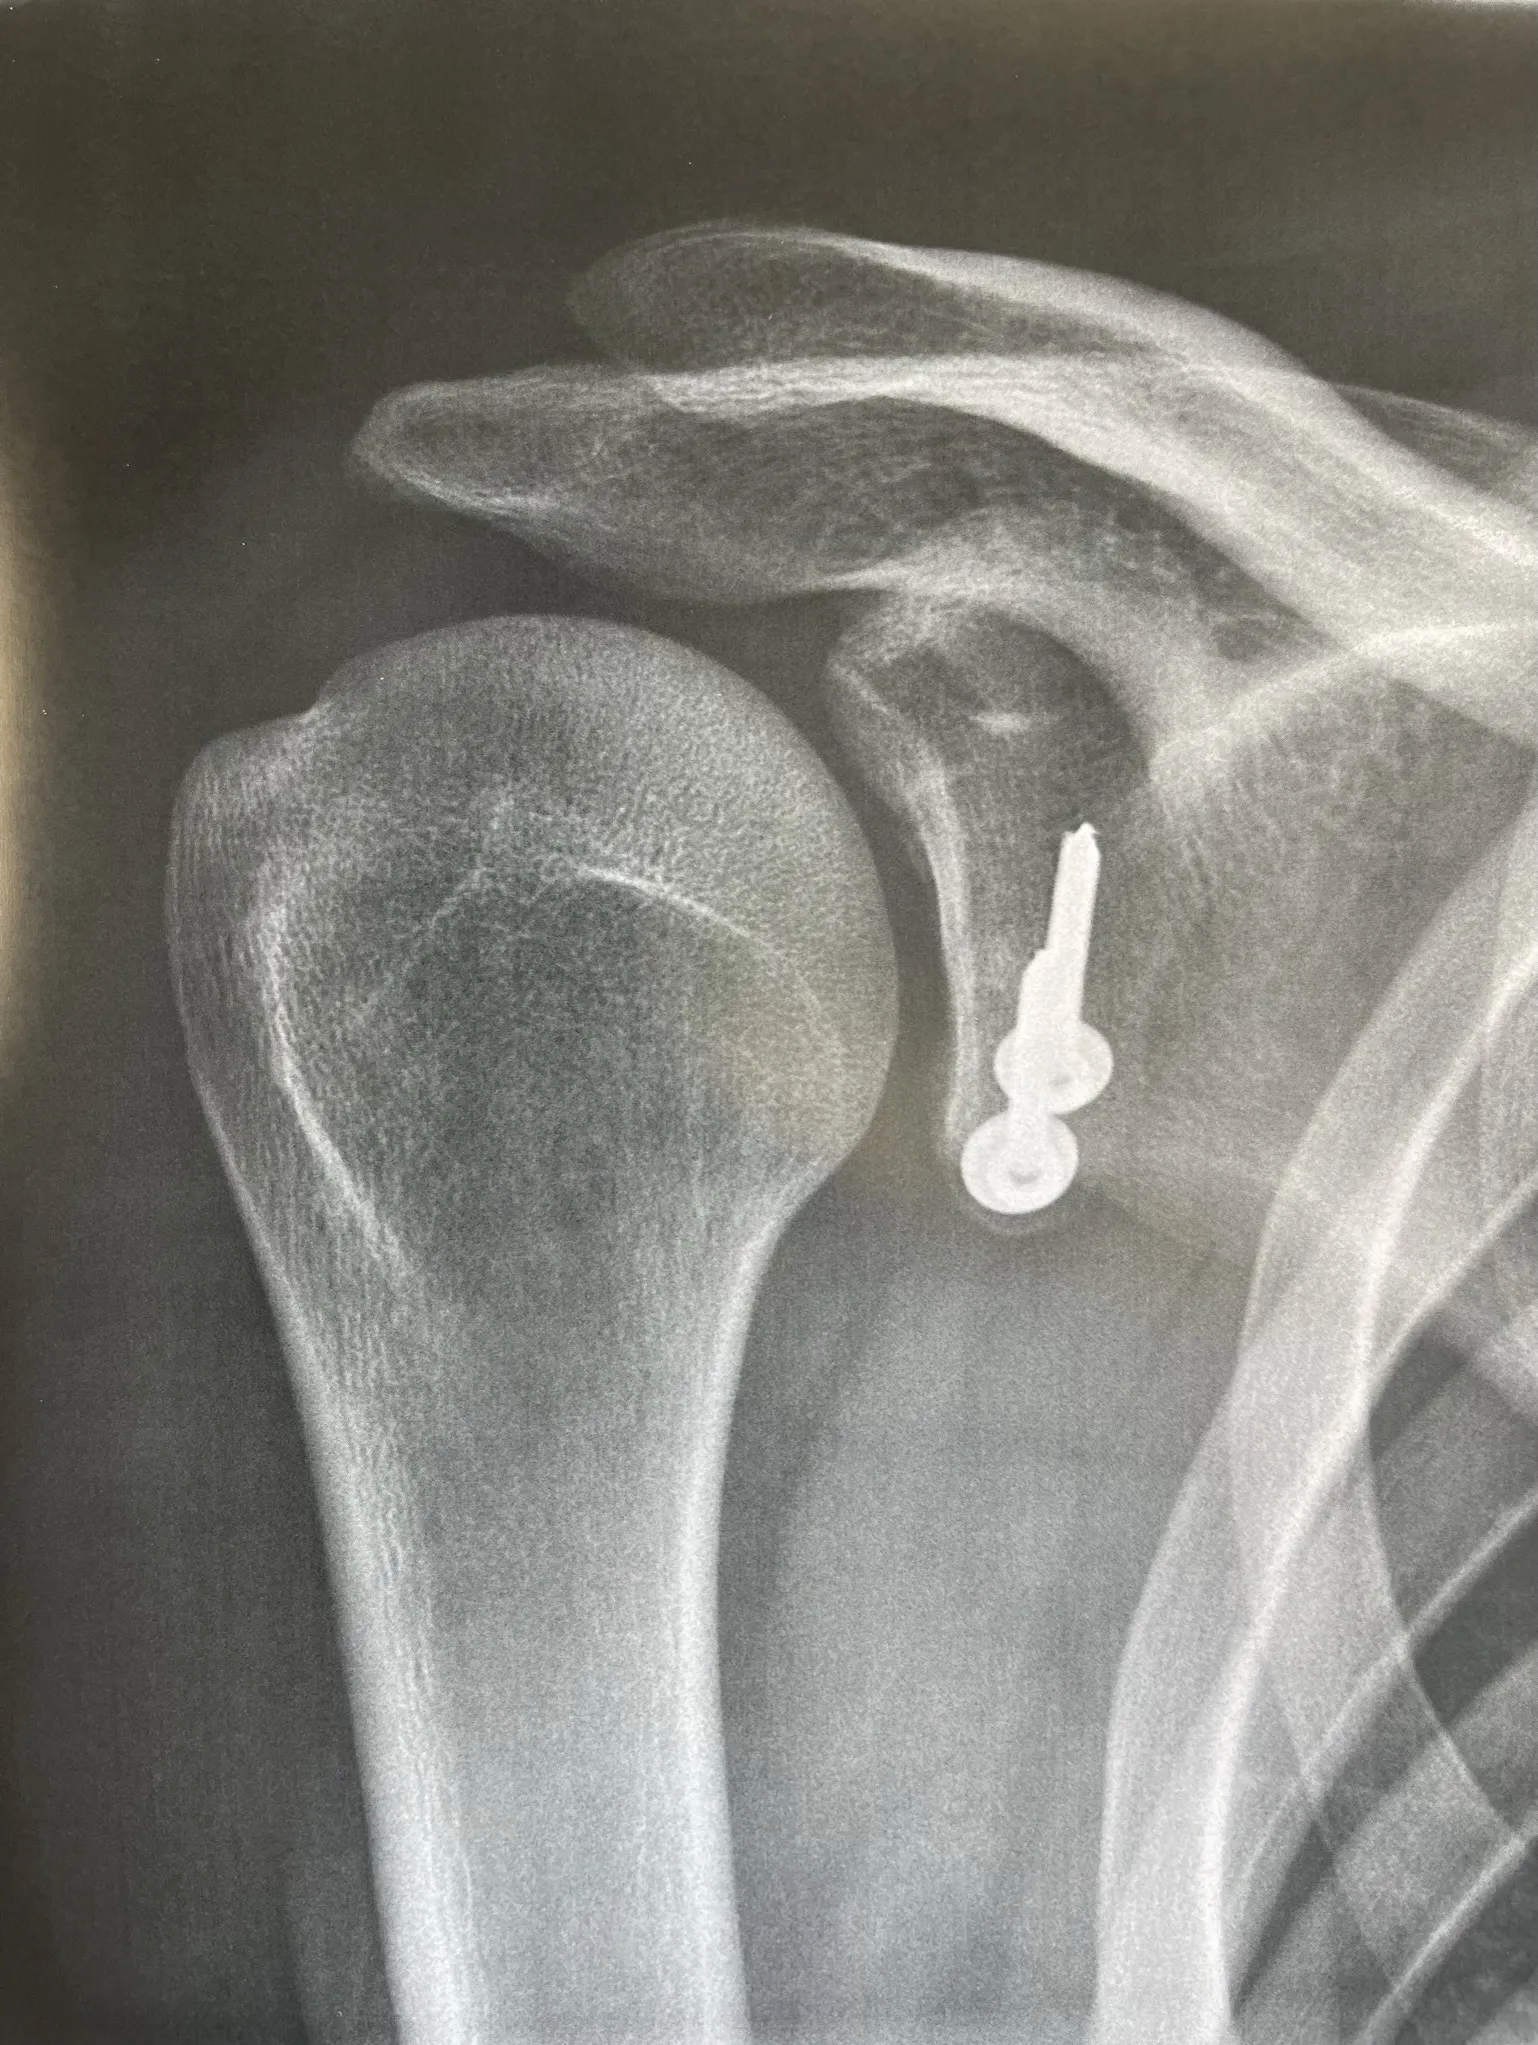

La butée coracoïdienne :

Cette intervention consiste à détacher un morceau d’os (la coracoïde) et à le refixer sur le bord antérieur de la glène afin d’obtenir un effet butée qui s'opposera à ce que la tête humérale ne reparte en avant de la glène. Cette butée est fixée par une ou deux vis ou par un système de boutons (endobutton). Elle est réalisée au travers d’une incision à la face antérieure de l’épaule de 5 cm environ.

La fixation de la butée peut se faire à l'aide de vis métalliques ou bien par des endobutton reliés par du fil très solide.

Depuis quelques années, cette technique peut également être réalisée sous arthroscopie par un chirurgien entrainé et formé. Votre chirurgien vous proposera cette technique si les lésions de votre épaule permettent de la réaliser.